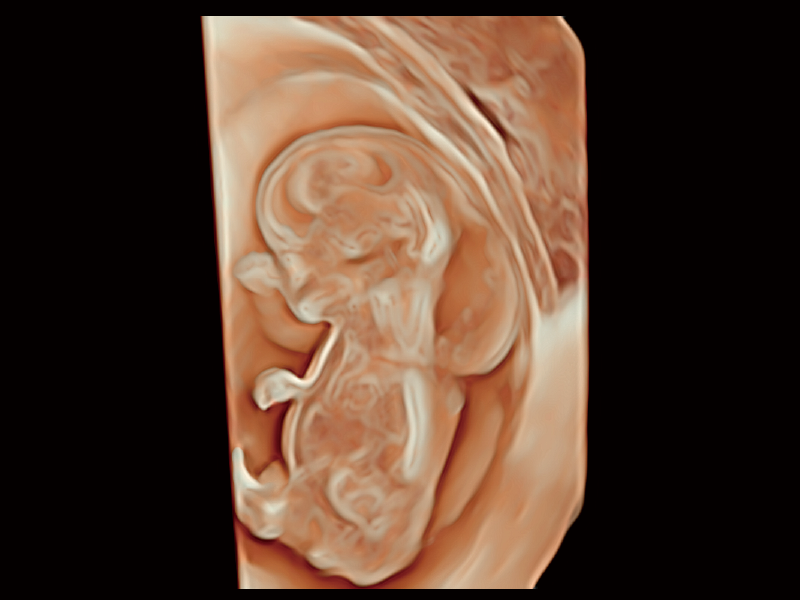

S-Live Studio

S-Fetus 5.0

FreeFusion